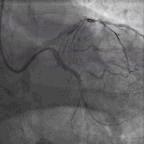

考虑前降支为此次胸痛的罪犯血管,尽管处理起来风险很大,最终还是决定一搏。两条导丝分别置入前降支和回旋支,用双导丝球囊Scoreflex(3.0*10)扩张(图4)后植入Xience V(4.0*12)支架1枚(图5),术后患者未出现慢血流和无复流(图6),同时胸痛缓解。

图4. 双导丝球囊Scoreflex(3.0*10)扩张

图5. 植入Xience V(4.0*12)支架

图6. PCI过程